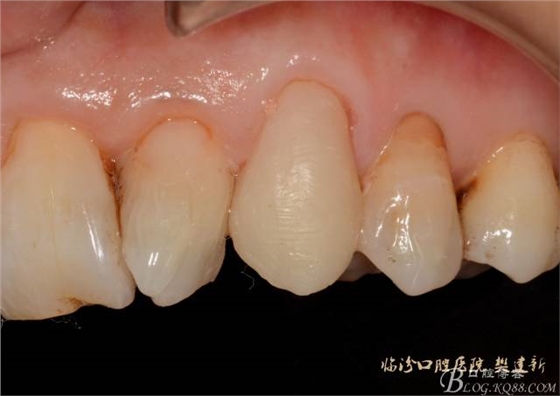

口內(nèi)檢查: 23殘根,位于齦上3MM,根管口探無反應(yīng),叩(+-),無松動,牙周無紅腫.X片示:23根管無阻射,根尖骨密度降低.11.12.13頸部楔形缺損,探敏感,牙髓活力正常.全口牙結(jié)石色素(+).

圖123口內(nèi)修復(fù)前情況:殘根位于齦上3MM,牙周無紅腫.